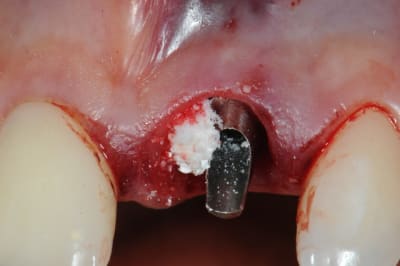

1 implantation

je n'étais pas du tout sure de le mettre car je n'avais qu'à peine 3à4 mm d'ancrage en apical.

je me suis fais un peu violence pour essayer tout de même quitte à perdre l'implant.

j'ai surtout été très surpris par l'excellente stabilité primaire malgré le peu d'os.

2 -3-4 implant et pilier en place

5-6-7-8-9-10 périotome-extraction-jauge- deuxième jauge-vérification de la profondeur par rapport aux collet des dents voisines-

séquence prothèse:

1-2-3 élaboration de la provisoire sur le pilier définitif et vérification des contacts occlusaux

4-5- pilier titane angulé à 7° et comblement du hiatus avec du Bioos-collagene qui supporte beaucoup mieux l'exposition que le Bioos simple

6-7-8 ayéh! j'ai fini pour aujourd'hui.

9 radio post op